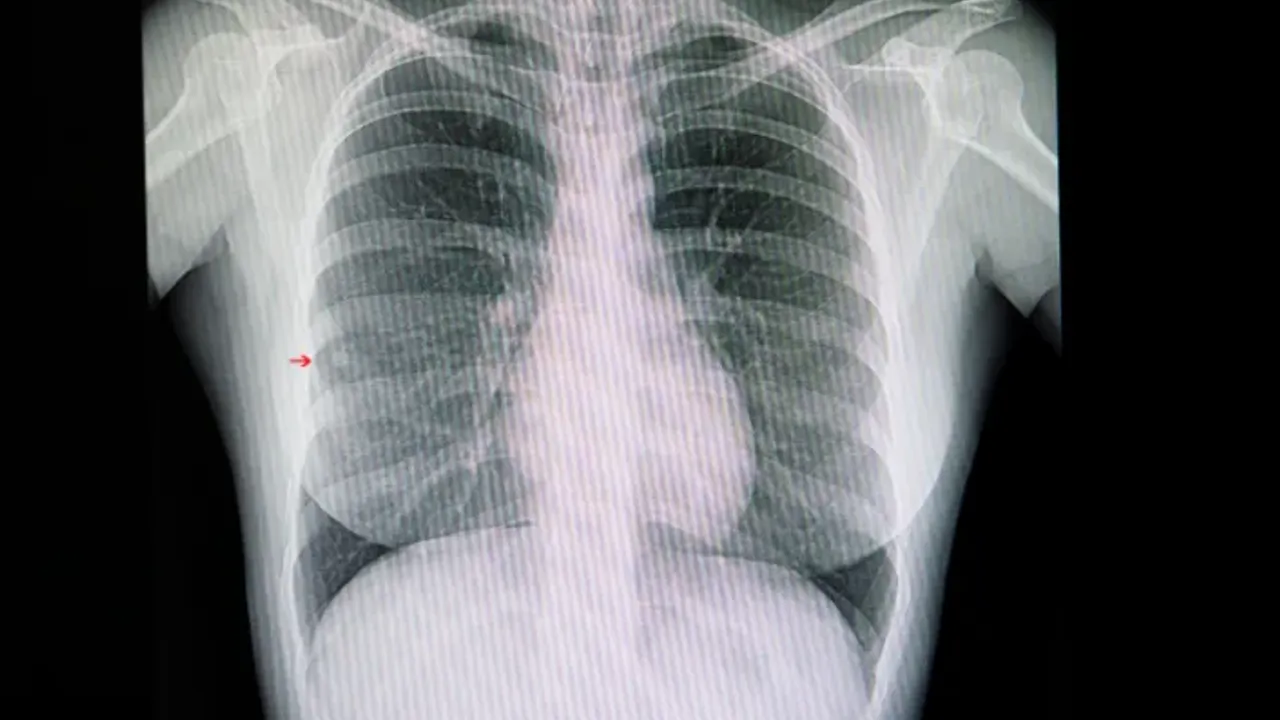

Günümüzde bilgisayarlı tomografi cihazlarının gelişmesiyle akciğerlerdeki nodülleri saptamanın kolaylaştığını ifade eden Liv Hospital Samsun'dan Uzm. Dr. Aziz Uluışık, "Kötü huylu (malign) nodüllere mümkün olduğunca erken dönemde tanı konulup ameliyat edilmesi halinde sağ kalım süresi artar. İyi (benign) nodüllerde ise gereksiz cerrahi girişimden ve buna bağlı oluşacak sorunlardan kaçınmak gerekir. Bu nedenle nodül saptandığında nasıl bir karar verileceği çok önemlidir. Günümüzde bilgisayarlı tomografi (BT) cihazlarının gelişmesi ve tomografi çekilen hasta sayısı artması sayesinde akciğerlerdeki nodülleri saptamak kolaylaştı. Akciğer tomografilerinin yaklaşık yüzde 30'unda bir veya birden fazla nodül saptama ihtimali vardır. Ancak bunların önemli mi, önemsiz mi, kötü mü yoksa iyi huylu mu olduğuna karar vermek bazı durumlarda zor olabiliyor" diye konuştu.

Uzm. Dr. Aziz Uluışık, öncelikle görülen nodülün boyutunun çok önemli olduğunun altını çizerek, "3 mm ve daha küçük nodüllerin kansere bağlı olma ihtimali yaklaşık yüzde 0,2 gibi düşük bir orandadır. 8-20 mm arasındakilerde bu ihtimal yüzde 18'e çıkarken, 20 mm'den büyük nodüllerde yüzde 64'den fazladır. Saptanan bir nodülün takibinde eski tomografiler ile karşılaştırmak önemlidir. Nodül boyutunda yüzde 25'den fazla bir artış olması kanser riskinin yüksek olduğuna işaret eder. Boyutundan sonra nodülün kenarlarının düzgün olup olmadığına bakmak gerekir. Kenarı düzensiz olan nodüllerin kanser riski 5 kat fazladır. Nodülün içinde kireçlenme bulunması, çoğunlukla iyi huylu olduğu anlamına gelir. Genellikle 2-3 yıl, bazı durumlarda ise 5 yıllık izlemde eğer nodülde bir değişiklik yoksa ileri incelemeye gerek yoktur" açıklamasında bulundu.

Akciğer grafisinde ya da tomografide büyüme saptanan her nodül olgusunda sakıncalı bir durum (kontrendikasyon) yoksa doku tanısının elde edilmesi gerektiğini söyleyen Uluışık, "Büyüme saptanan her nodülde kanser ihtimali arttığı için radyolojik veya cerrahi biyopsi gerekir. Kanser ihtimali yüksek nodül varlığı ve riskli hastalarda ameliyat ile nodülü çıkarmak hayat kurtarıcı olabilir. Sigara kullanmış ya da halen kullanmakta olan, 40 yaş üzeri ve de kendisinde ve 1. derecede akrabalarında kanser öyküsü bulunan kişiler yüksek risk grubuna girer. Özellikle ileri yaş ve içilen sigara miktarının çokluğu ile kanser potansiyeli artar. Hekim görülen nodülün özelliklerine bakarak kanser riskini tayin eder. Buna göre de hastanın tomografi ile takip edilmesi mi, yoksa biyopsiye mi gönderilmesi gerektiğine karar verir. Bu karar hasta adına hayati olabilir. Her hasta ve nodül için aynı senaryo geçerli olmayabilir. Bu yüzden sayılan özelliklerin sadece ihtimal üzerinden değerlendirildiği ve her zaman için düşük ihtimalli durumlarla da karşılaşılabileceği unutulmamalıdır" şeklinde konuştu.